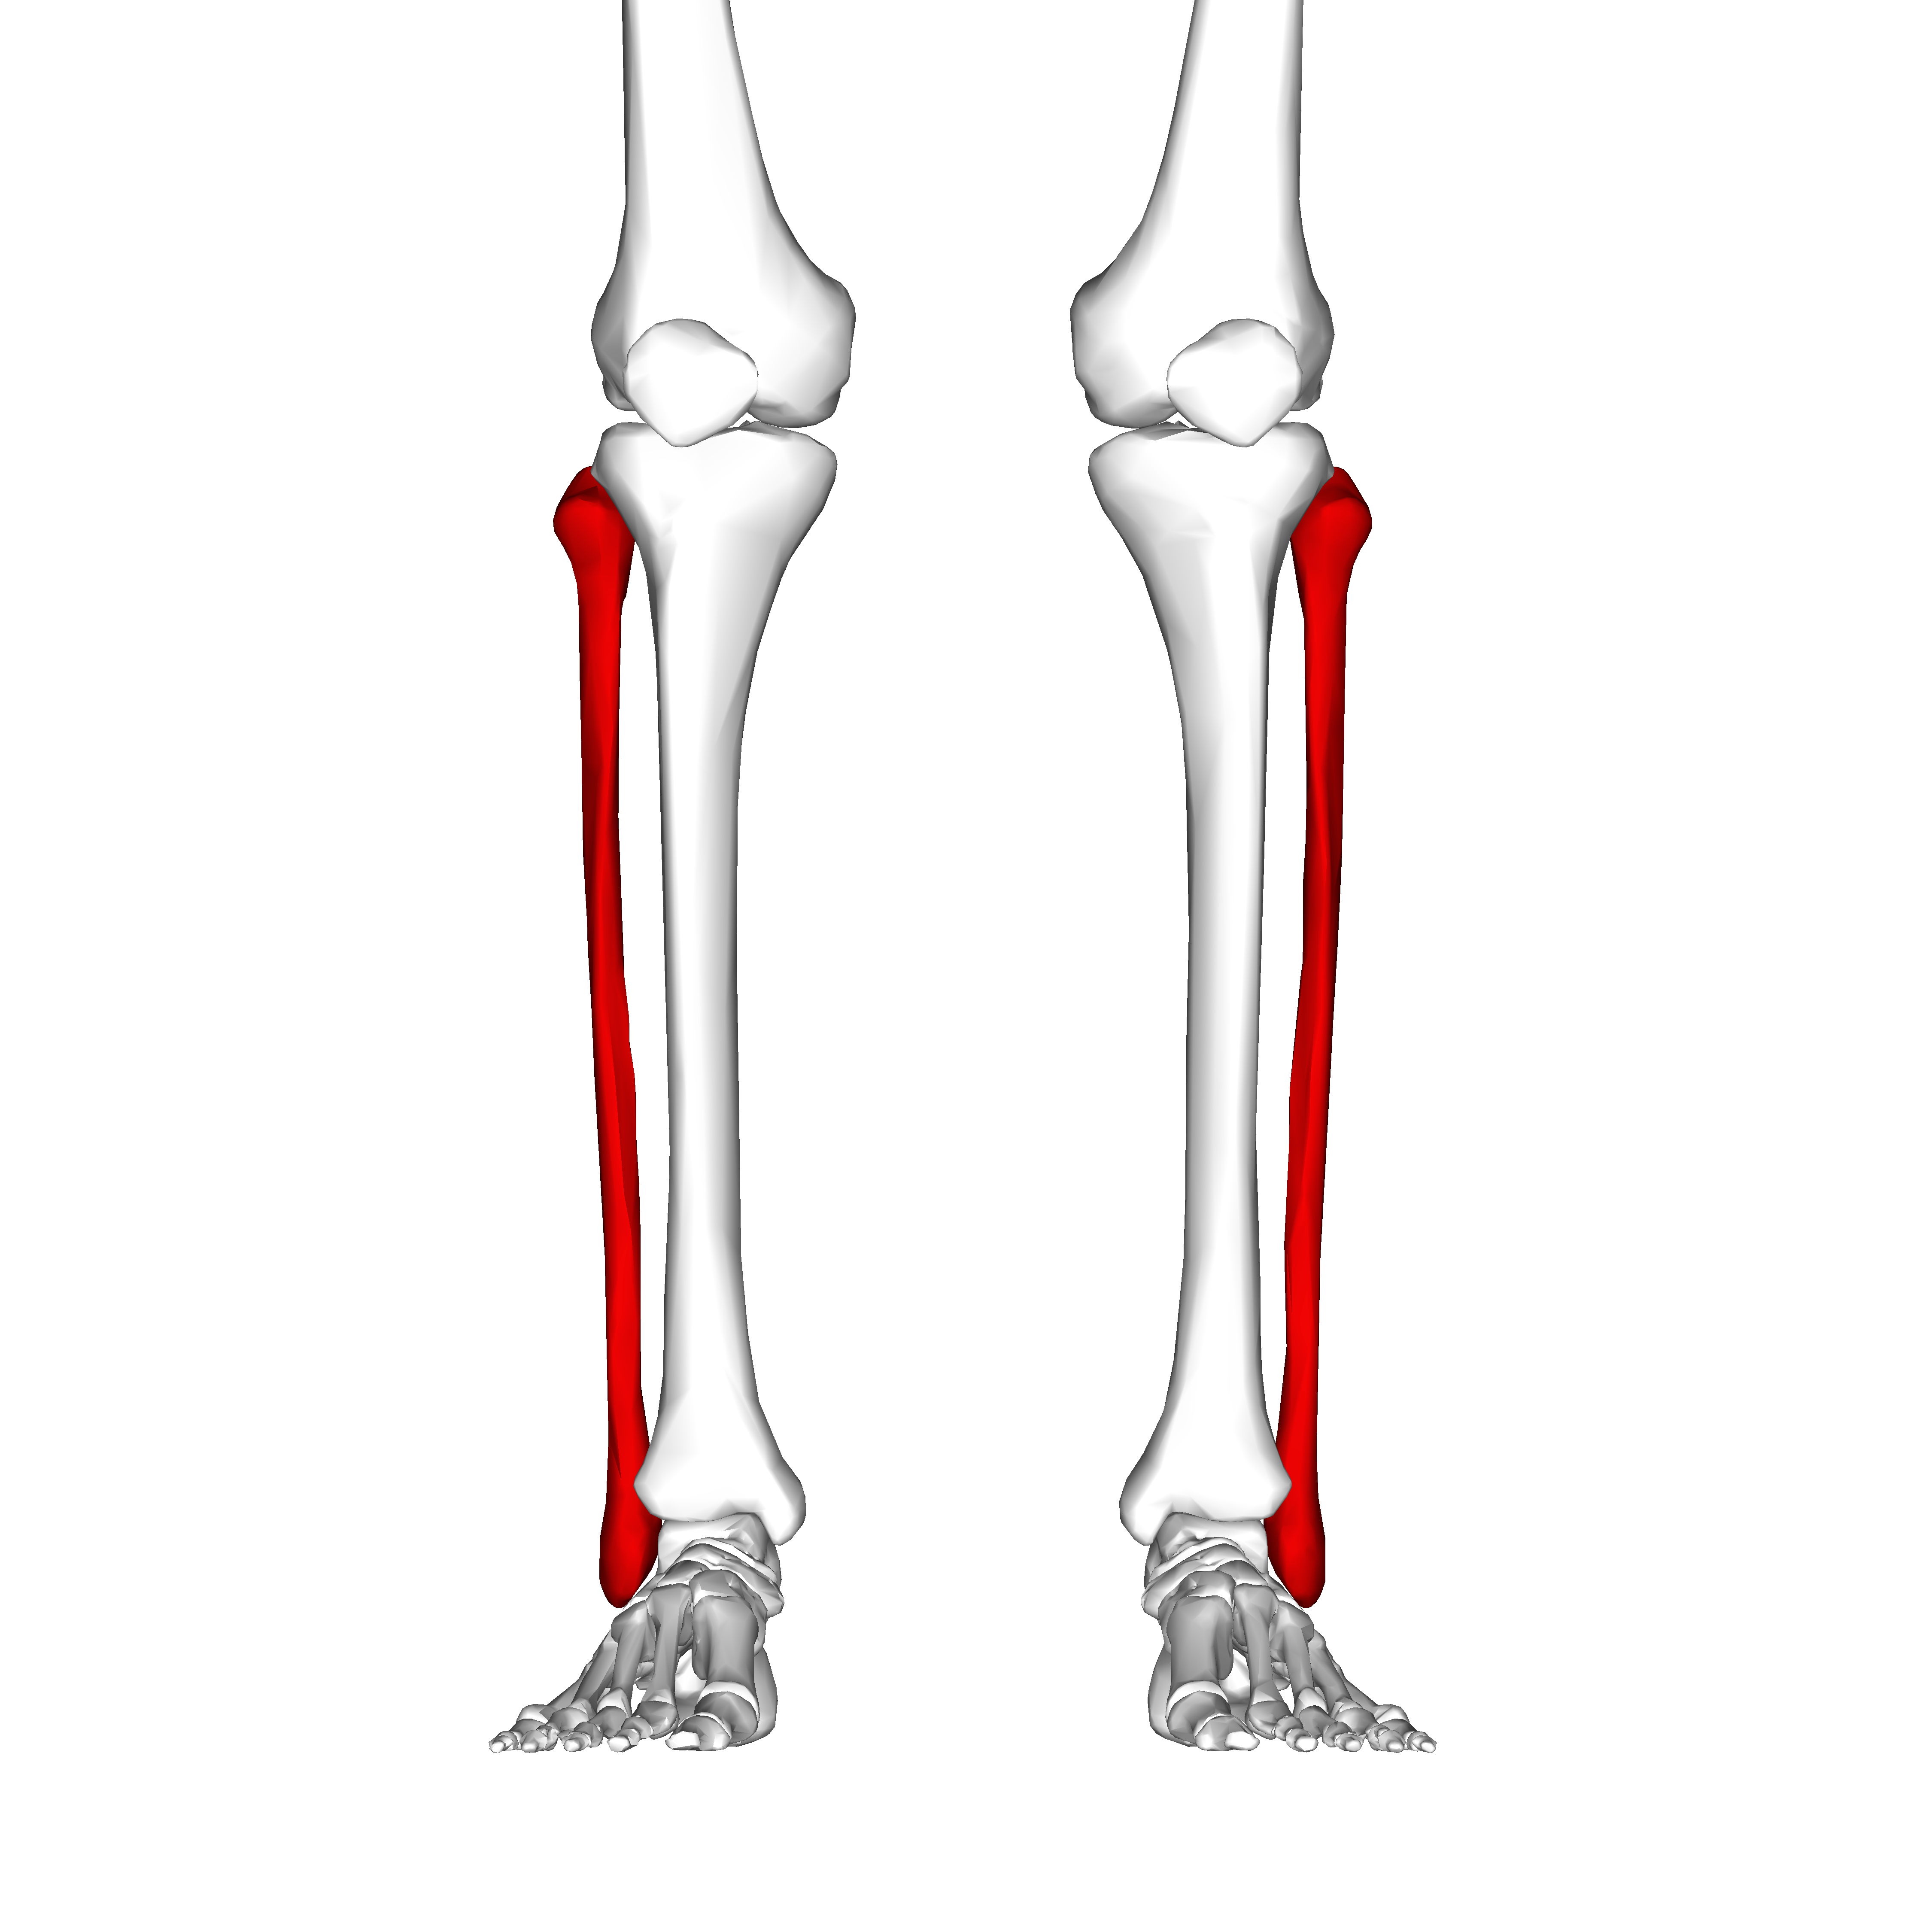

Tibia (shaft) and Fibula (shaft) Work Bulletin Boards, Skeleton Anatomy …

Tibia and Fibula (1) in 2022 | Anatomy bones, Human anatomy and …

Tibia and fibula | Anatomy bones, Rib cage anatomy, Anatomy

Tibia and Fibula Osteology of the Leg and Knee